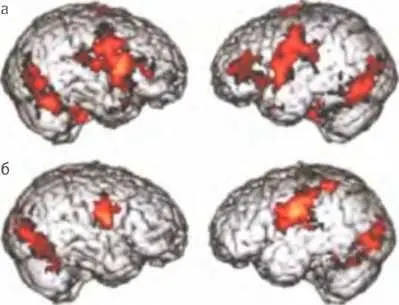

Активность мозга здорового ребенка, в том числе активность зеркальных нейронов в лобных долях (а), и пониженная активность мозга ребенка, страдающего аутизмом (б).

Результаты некоторых исследований, в которых использовались методы нейровизуализации, указывают (хотя и небесспорно) на то, что “психологическая слепота” аутистов может быть, по крайней мере отчасти, связана с нарушениями в системе зеркальных нейронов. В рамках одного такого исследования ученые сравнили активность зеркальных нейронов у детей, обладающих выдающимися способностями, но страдающих аутизмом, и у контрольной группы здоровых детей. Тех и других исследовали с помощью ФМРТ в то время, когда дети наблюдали за эмоциональными выражениями лиц и пытались их имитировать. Хотя имитация давалась детям из обеих групп одинаково хорошо, у детей-аутистов не наблюдалось никакой или почти никакой активности зеркальных нейронов в зоне коры лобных долей, играющей ключевую роль в обработке информации, связанной с эмоциями. Дети, у которых расстройство было особенно тяжелым, демонстрировали самый низкий уровень активность этих нейронов 9. Другое исследование показало, что у взрослых, страдающих различными формами аутизма, кора больших полушарий в зонах, связанных с активностью зеркальных нейронов, тоньше, чем у взрослых из контрольной группы 10. Это вполне логично: аутизм — это прежде всего расстройство коммуникативных способностей, то есть нарушение способности делиться чувствами, мнениями и знаниями с другими людьми.